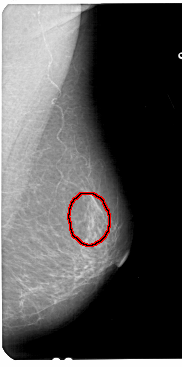

FILE: A_1433_1.RIGHT_MLO.OVERLAY

TOTAL_ABNORMALITIES 1

ABNORMALITY 1

LESION_TYPE CALCIFICATION TYPE PUNCTATE DISTRIBUTION SEGMENTAL

ASSESSMENT 2

SUBTLETY 3

PATHOLOGY BENIGN

TOTAL_OUTLINES 1

BOUNDARY